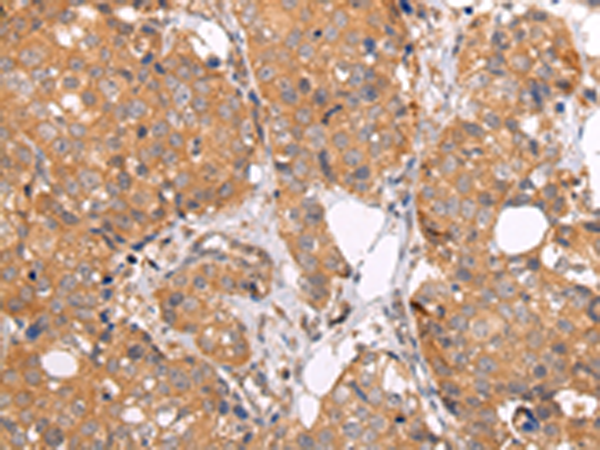

分类: 科研抗体货号: P12470别名: MRP; ABCC; GS-X; MRP1; ABC29应用: WB,IHC反应种属: Human